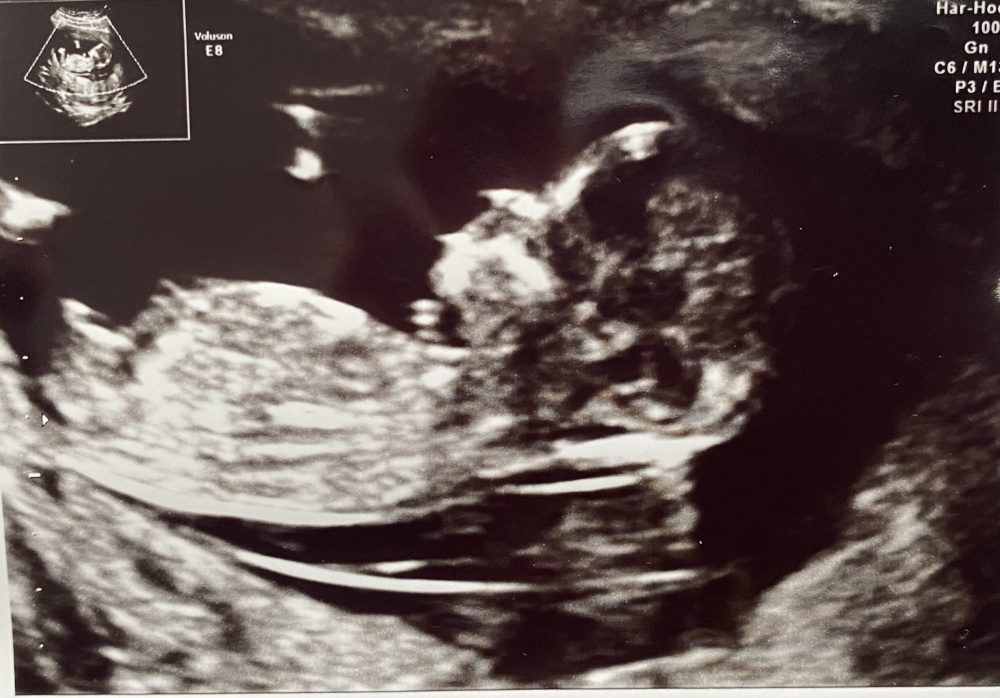

ich war am Montag beim ETS und habe dieses Bild bekommen. Nach meiner Rechnung 12+2.

Der Arzt hat ohne dass ich gefragt habe, „rausgehauen“ was es seiner Meinung 100% wird. Was denkt ihr denn?

Auf der einen Seite schaut es für mich wie ein Penis aus, auf der anderen denke ich einen Nub parallel zur Wirbelsäule zu sehen.

Das ist übrigens nur der Rumpf.

„Den NIPT können Sie ruhig machen, aber es wird sowieso ein Junge“ 😉.